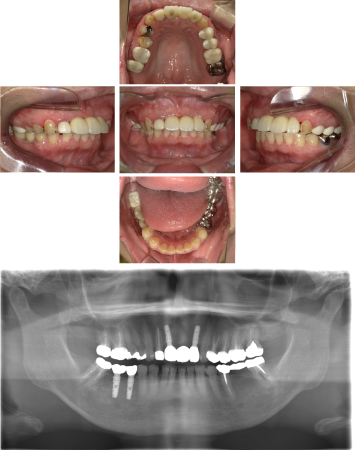

30代 女性 奥歯 インプラントGBR

| 年代・性別 | 30代・女性 |

| 治療回数 | 1回 ※術前治療・検査除く |

| 治療期間 | 5ヶ月 |

| 料金 | ¥60,000(税込) |

GBR(Guided Bone Regeneration:骨再生誘導法)とは、インプラント治療において、骨の厚みや高さが足りない場合に行う歯槽骨を再生する方法です。骨量不足の患者様でも、骨造成を行うことでインプラントの埋入に必要な骨の高さや厚みが得られます。 GBR(再生誘導法)は、骨が痩せて十分な骨量が確保できない患者様に、骨の再生によってインプラントの埋入を可能にする治療方法の一つです そのような骨が欠損した部分では、骨を作る「骨芽細胞」よりも、骨にならない「線維芽細胞」の方が増殖しやすいという特徴があります。そのためGBRでは、骨形成の妨げになる繊維芽細胞の侵入を防ぐため、骨を増やしたい部分を「メンブレン」という人工膜で覆い、その中に自家骨や人工の骨補填材を詰めて骨芽細胞の増殖を促します。 |

| 副作用 | 術後に腫れ・痛みが出る可能性がある。 |